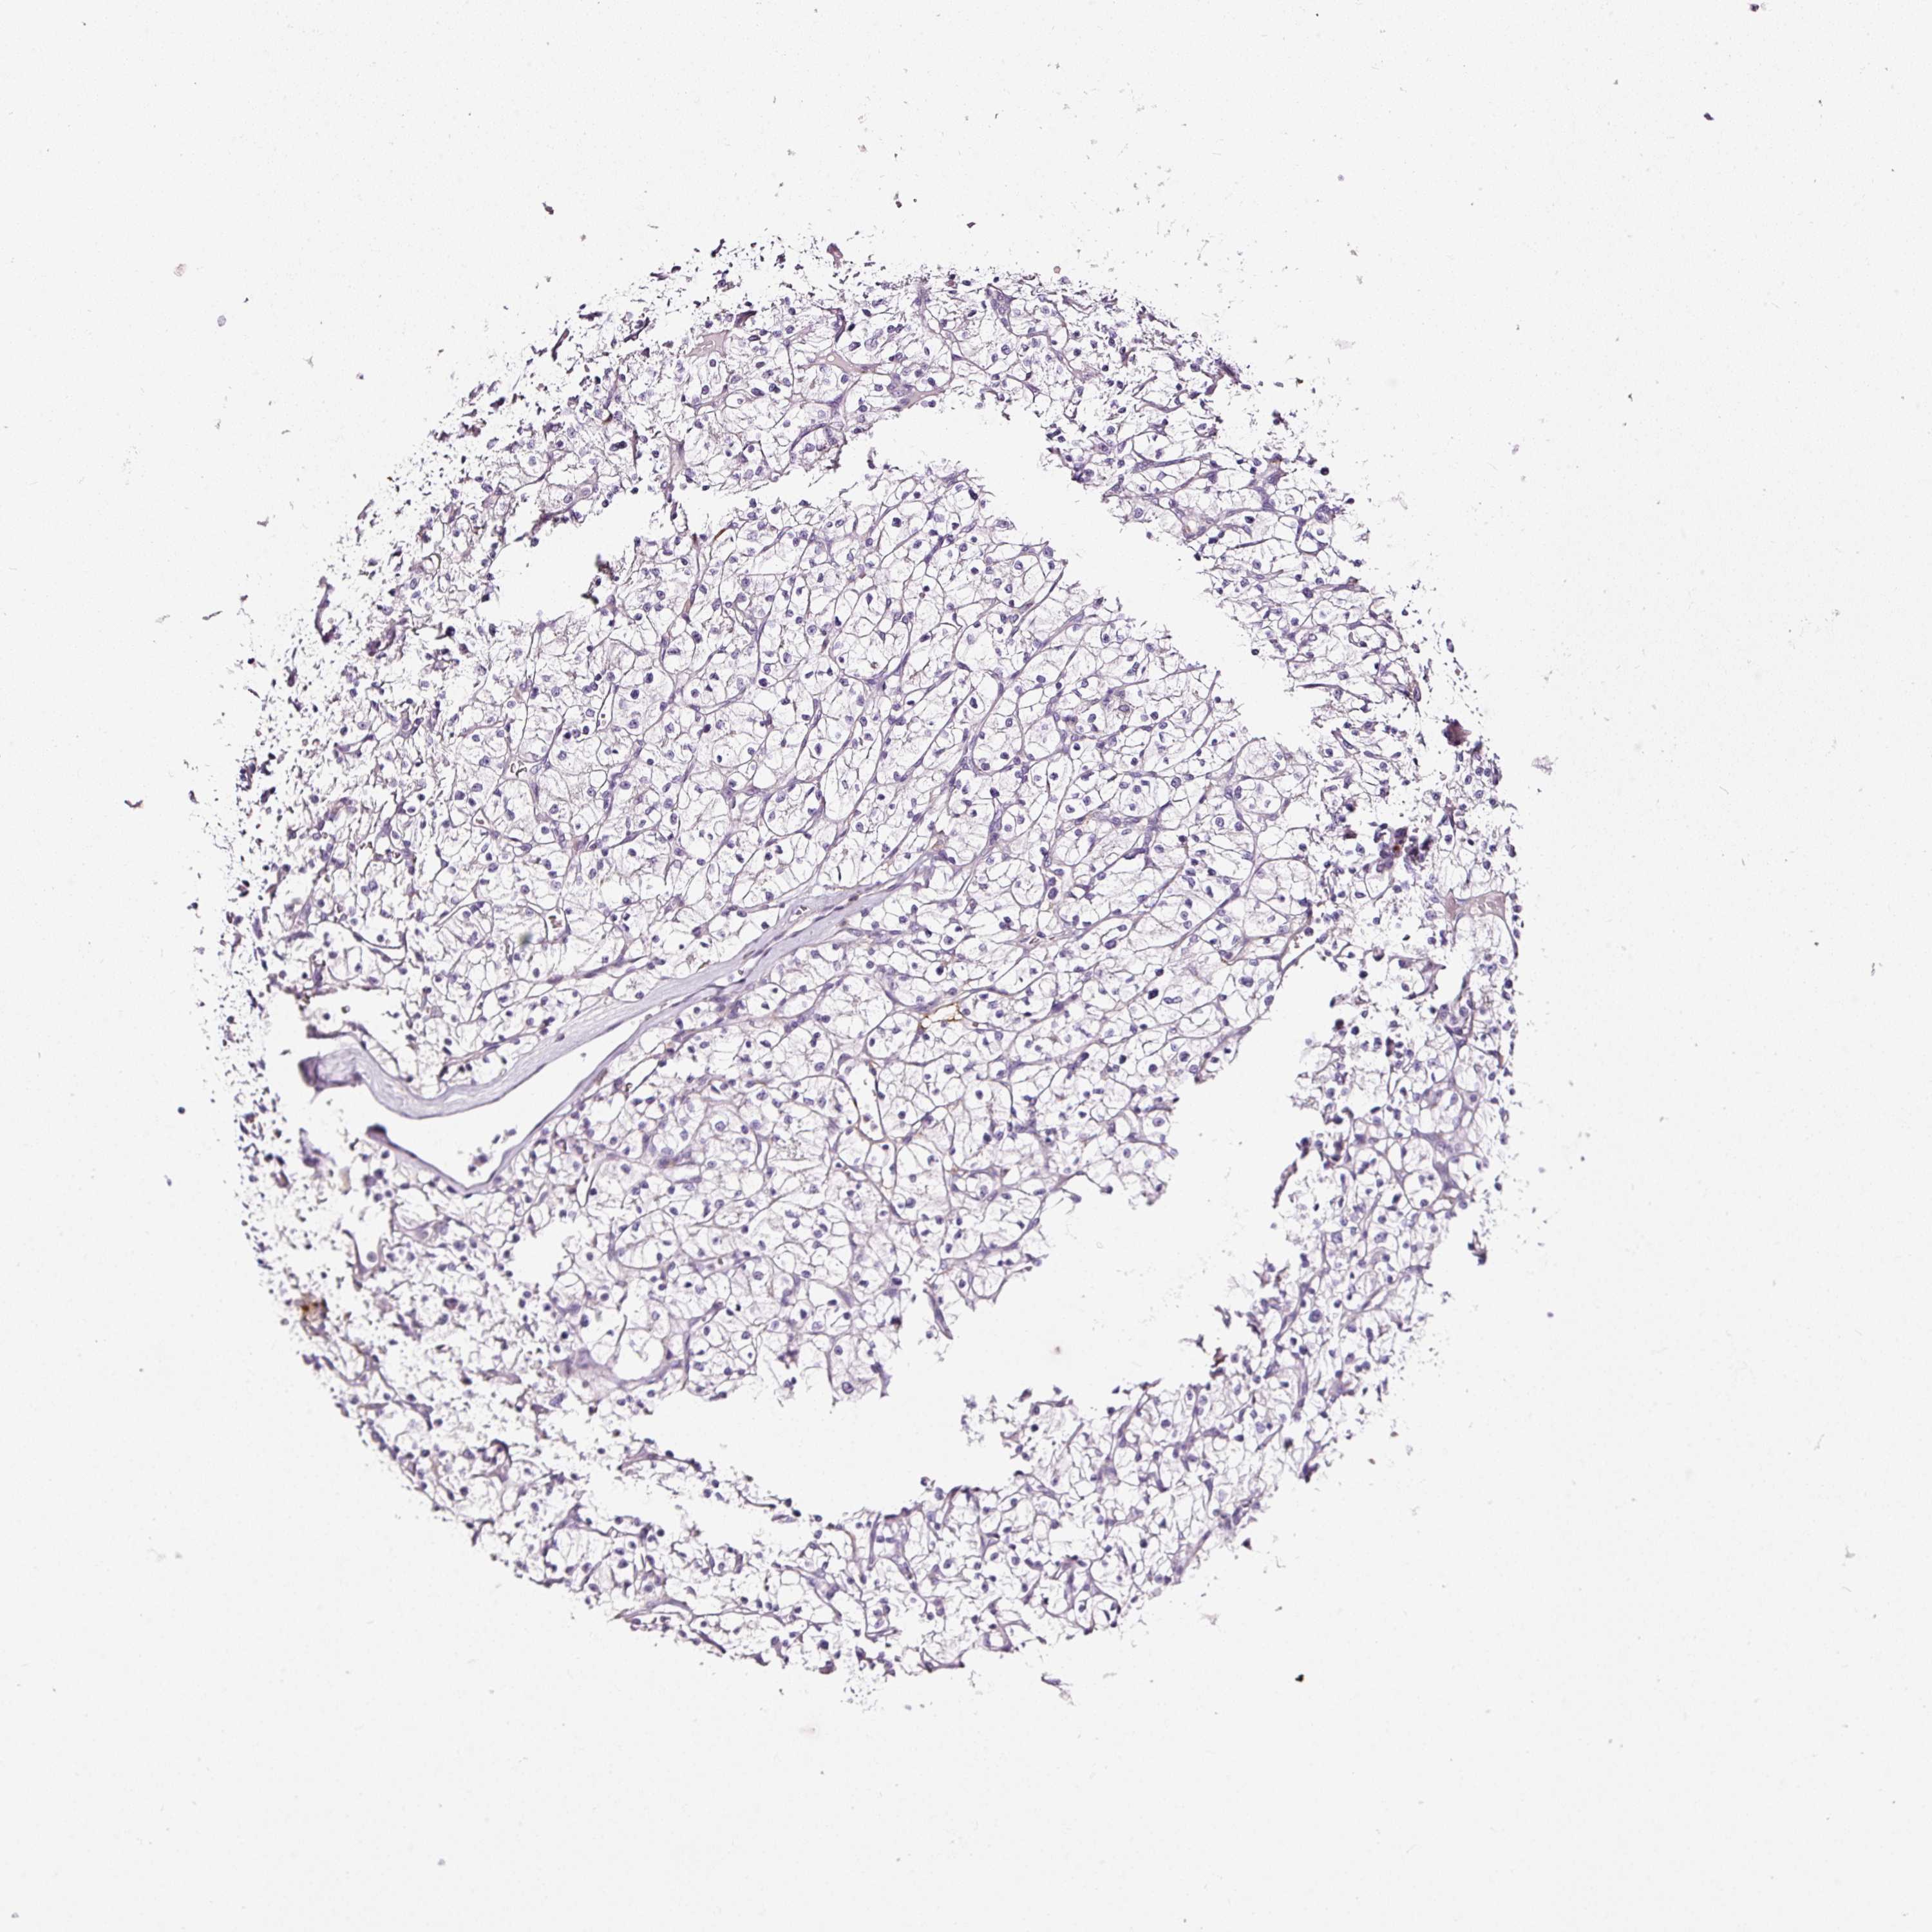

KIDNEY RENAL CLEAR CELL CARCINOMA (VALIDATION) - Interactive survival scatter ploti

The Survival Scatter plot shows the clinical status (i.e. dead or alive) for all individuals in the patient cohort, based on the same data that underlies the corresponding Kaplan-Meier plots. Patients that are alive at last time for follow-up are shown in blue and patients who have died during the study are shown in red.

The x-axis shows the expression levels (FPKM) of the investigated gene in the tumor tissue at the time of diagnosis. The y-axis shows the follow-up time after diagnosis (years). Both axes are complimented with kernel density curves demonstrating the data density over the axes. The top density plot shows the expression levels (FPKM) distribution among dead (red) and alive patients (blue). The right density plot shows the data density of the survived years of dead patients with high and low expression levels respectively, stratified using the cutoff indicated by the vertical dashed line through the Survival Scatter plot. This cutoff is automatically defined based on the FPKM cutoff that minimizes the p-score. The cutoff can be changed by dragging the vertical line or by entering a cutoff value in the square labeled "Current cut-off".

Under the Survival Scatter plot the p-score landscape (black curve; left axis) is shown together with dead median separation (red curve; right axis). Dead median separation is the difference in median mRNA expression between patients who have died with high and low expression, respectively. It is calculated as follows: median FPKM expression of dead patients with high expression - median FPKM expression of dead patients with low expression. This is intended to aid the user in visually exploring custom cutoffs and the associated p-scores and dead median separation.

Individual patient data is displayed and can be filtered by clicking on one or more of the category buttons on the top of the page. Categories describing expression level and patient information include: high, low, alive, dead, female, male and tumor stages. The scale of the x-axis can be toggled between linear and log-scale by clicking on the "x log" button. Mouse-over function shows TCGA ID, patient information and mRNA expression (FPKM) for each patient.

& Survival analysisi

Kaplan-Meier plots summarize results from analysis of correlation between mRNA expression level and patient survival. Patients were divided based on level of expression into one of the two groups "low" (under cut off) or "high" (over cut off). X-axis shows time for survival (years) and y-axis shows the probability of survival, where 1.0 corresponds to 100 percent.

CYB561A3 is not prognostic in Kidney Renal Clear Cell Carcinoma (validation)

Best expression cut offi

Based on the FPKM value of each gene, patients were classified into two groups and association between prognosis (survival) and gene expression (FPKM) was examined. The best expression cut-off refers the FPKM value that yields maximal difference with regard to survival between the two groups at the lowest log-rank P-value. Best expression cut-off was selected based on survival analysis .

When clicking on this number, the vertical dashed line indicating cut-off, the interactive survival plot, and the Kaplan-Meier curve will be adjusted to show results based on the best expression cut-off.

: 24.24

P scorei

Log-rank P value for Kaplan-Meier plot showing results from analysis of correlation between mRNA expression level and patient survival.

N/A

5-year survival highi

5-year survival for patients with higher expression than the expression cutoff.

For melanoma and glioma, 3-year survival is shown.

5-year survival lowi

5-year survival for patients with lower expression than the expression cutoff.

TCGA RNA samplesi

RNA-seq data is reported as average FPKM (number Fragments Per Kilobase of exon per Million reads), generated by the The Cancer Genome Atlas (TCGA) .

Normal distribution across the dataset is visualized with box plots, shown as median and 25th and 75th percentiles. Points are displayed as outliers if they are above or below 1.5 times the interquartile range. FPKM values of the individual samples are presented next to the box plot.

Average pTPM 27.4

Number of samples 100